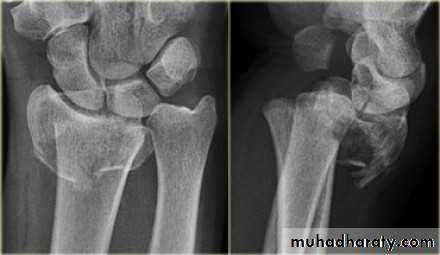

Upper limb

Fall on out stretched hand

xray

40 years male fall on out streched hand